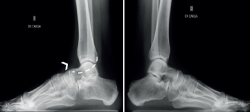

Por otro lado, debido al estudio de referencia de Harris(4), se cree que las coaliciones se asocian universalmente con la deformidad del pie plano. De este modo, todo pie plano infantil sintomático se trataría de una coalición. Sin embargo, solo alrededor de la mitad de las coaliciones se asocian con el pie plano(22) e incluso pueden asociarse con una deformidad del pie cavo(7,23,24,25) (Figura 1).

Figura 1. Paciente con coalición talocalcánea bilateral. A: pie derecho cavo-varo, sincondrosis y pie izquierdo; B: plano valgo, barra ósea; C: en la radiografía lateral izquierda se aprecia el c-sign y en la derecha se aprecia la ausencia de la faceta medial.